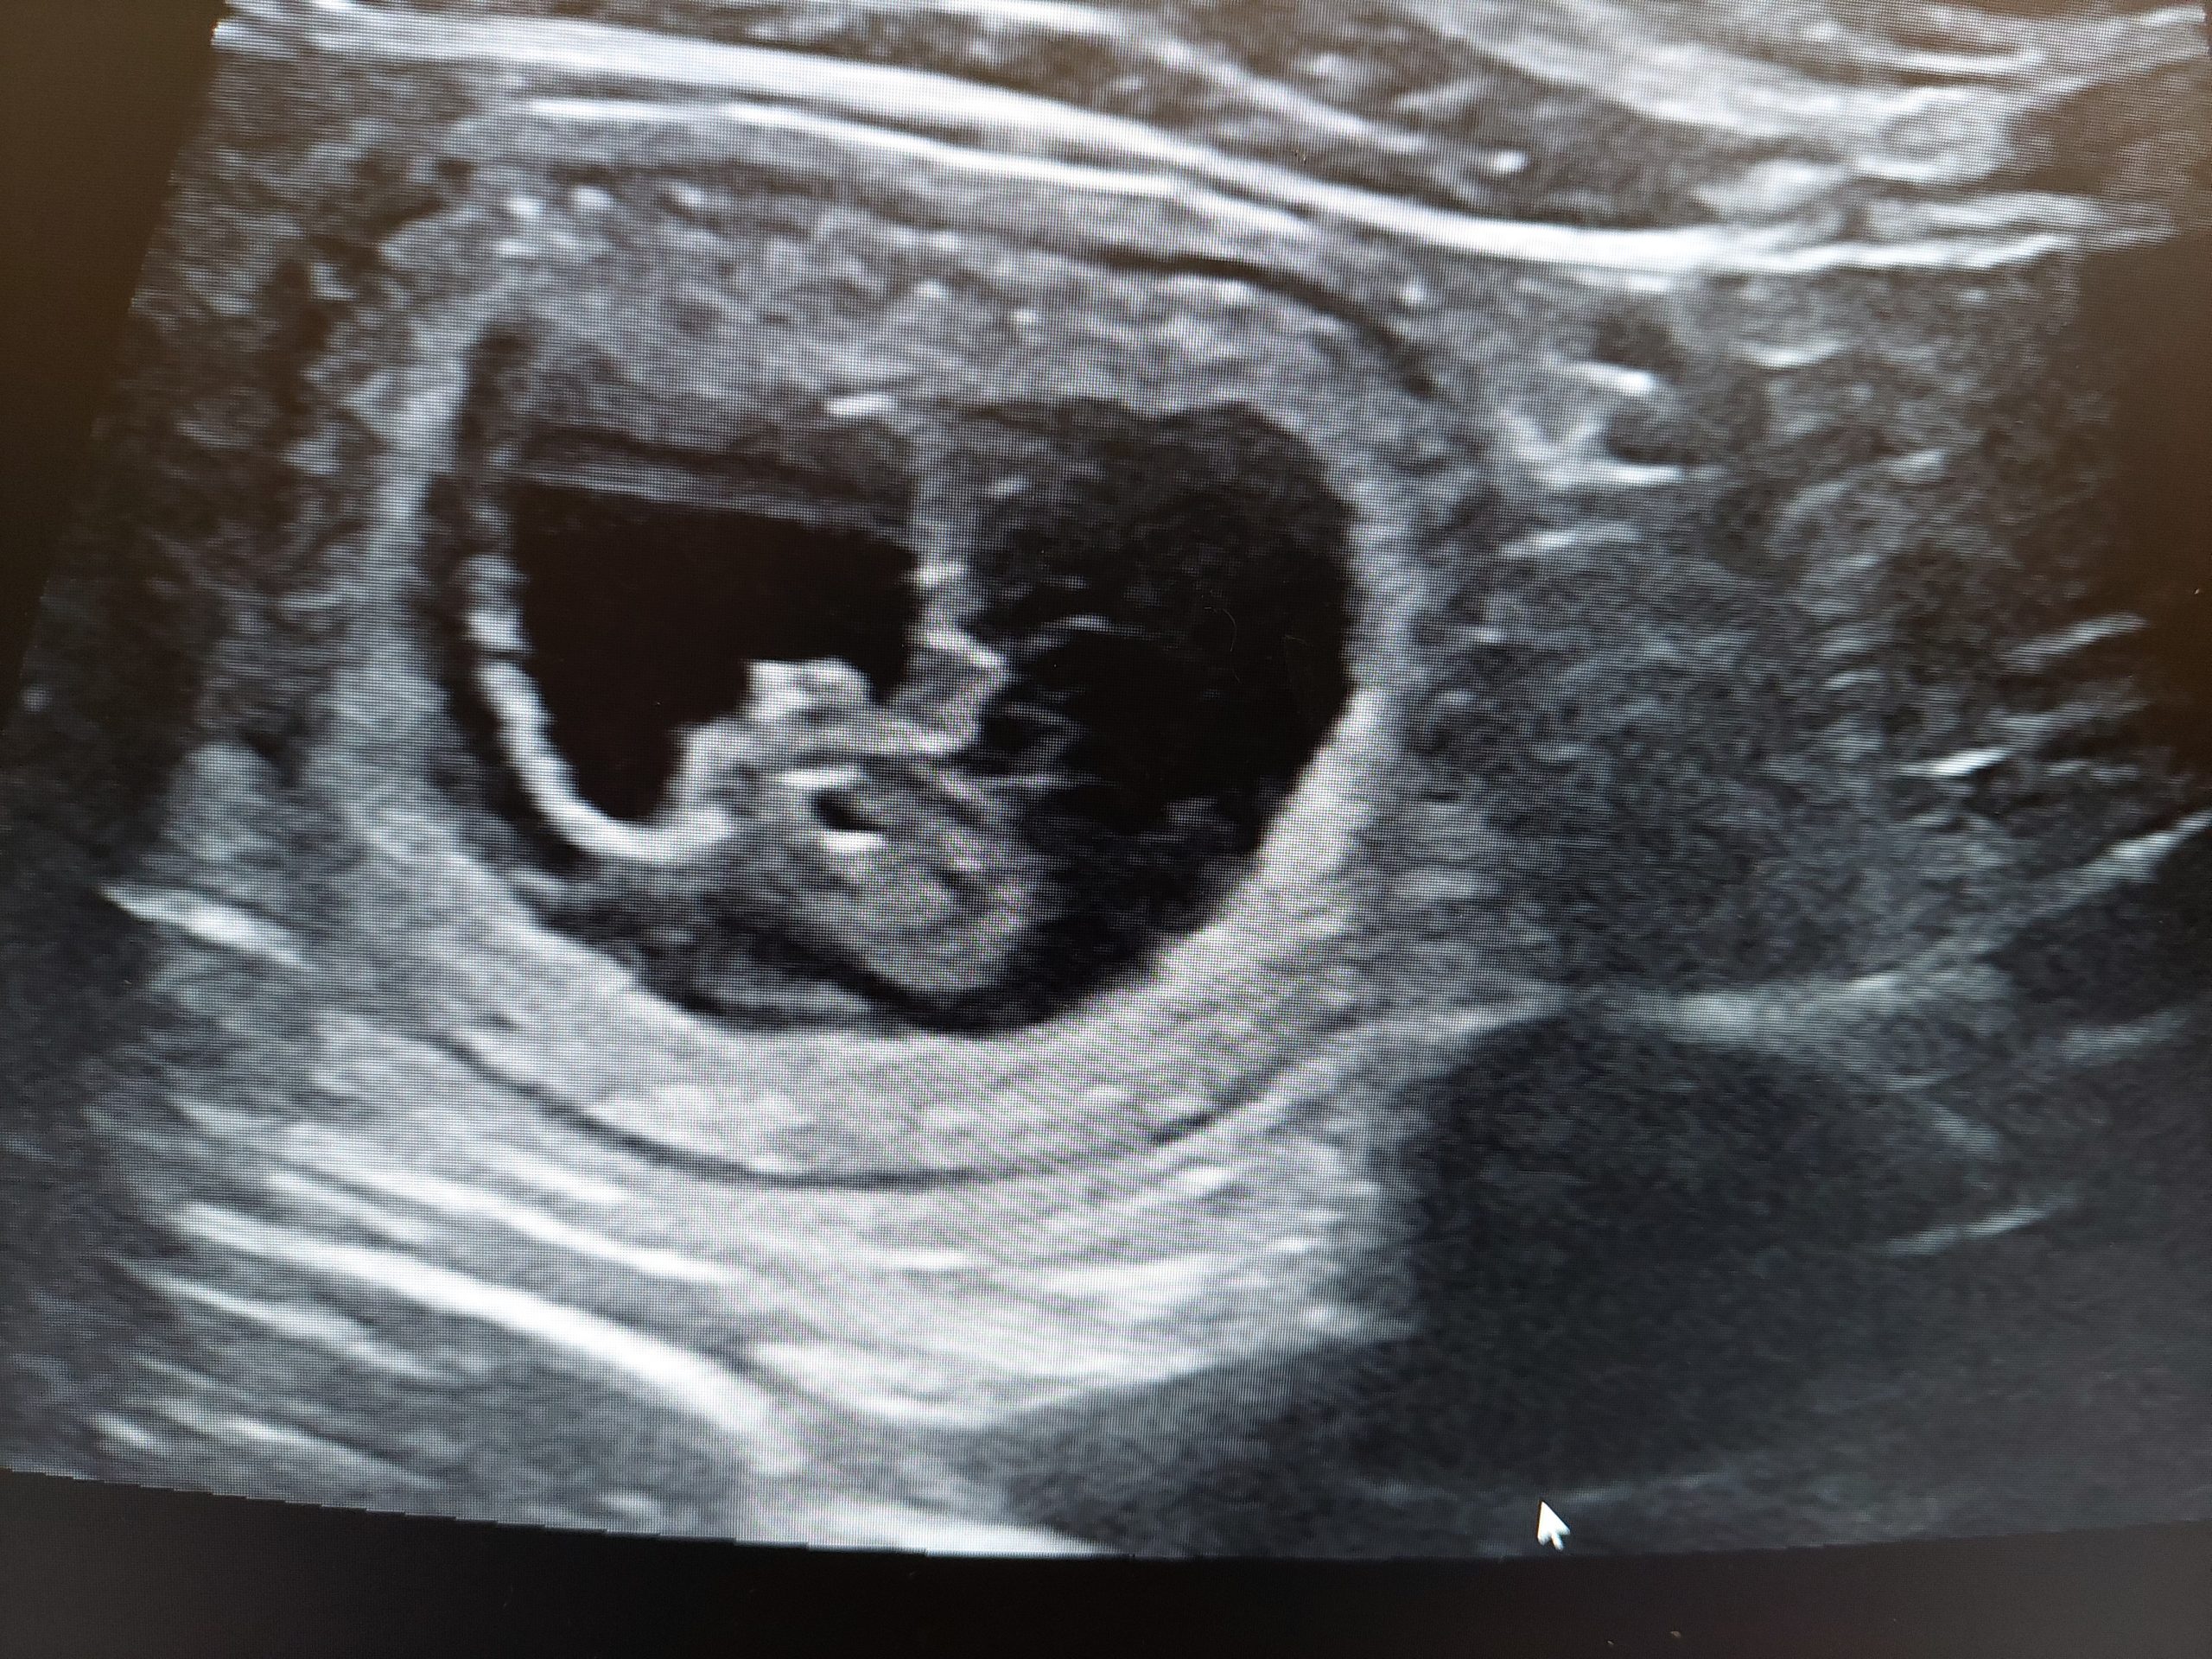

Bayerischer Gebirgsschweisshunden puppies born 19/08/2022. 3 males en 4 females. Mother Pleun (Bernis Van Jagthuis Gerven) and father Abe ( Swawir Sfora Nemroda) regularly used for tracking owned by Herwi Hoenink kennel Van t’Rutbekerveld. All puppies have a new owner.